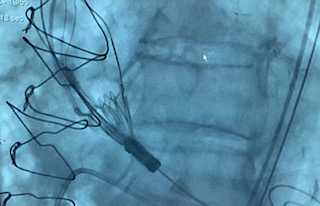

Liberación de una TAVI

Liberación TAV

Liberación TAVI